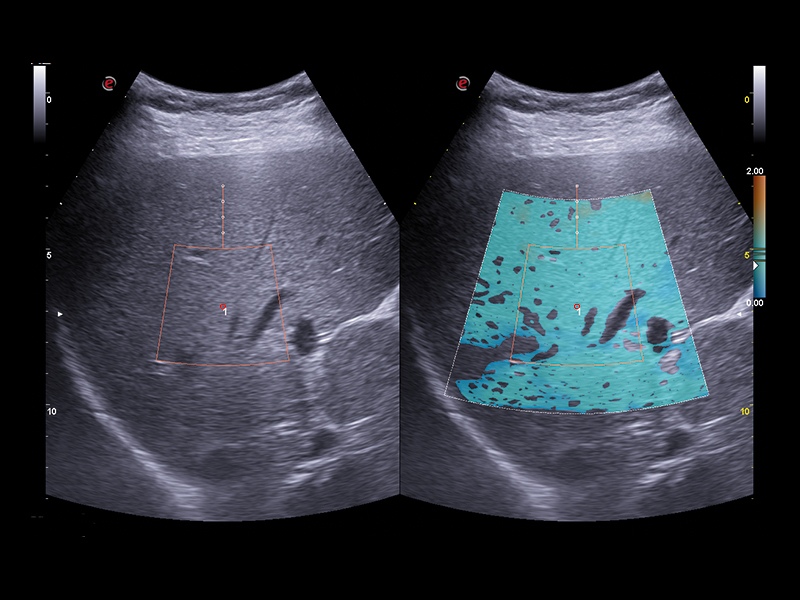

Esaote offers a comprehensive real-time multiparametric package to assess the liver tissue in a non-invasive way. QElaXto 2D, Esaote’s Shear Wave Elastosonography (SWE) technique enables stiffness mapping and provides a quantitative assessment of liver fibrosis.

A strong rejection algorithm associated with a dispersion map increases the quality and reliability of the measurements. QAI (Q Attenuation Imaging) is an ultrasound technique for the visualization and quantification of the attenuation along the liver depth provided by Esaote, to support the evaluation of fatty liver tissue and help in the steatosis assessment. The data are computed in a clear multiparametric report with a spider or bar-graph representation to obtain an overview of the liver condition at a glance.